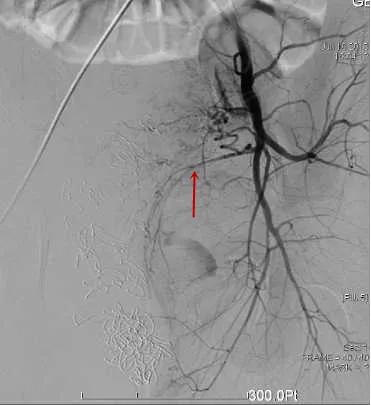

△造影找到出血动脉/找到出血责任动脉/精准栓塞后出血动脉已闭塞